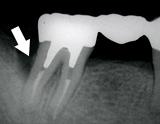

歯槽膿漏・X線写真 | ||

| 歯槽膿漏によって失われた骨(→印の部分)が再生しています。 | ![]() |

![]() |

【術前】 |

【術後】 |